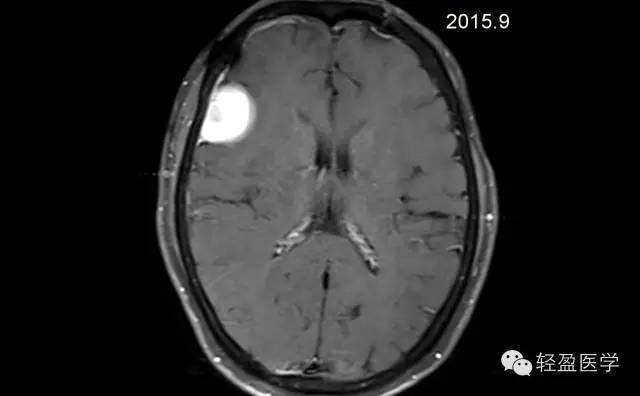

【病例】颅内肿瘤,脑内?脑外?

病理为:小细胞恶性肿瘤,考虑为(外周)原始神经外胚层肿瘤,(复发)。以下是病例结果及分析。